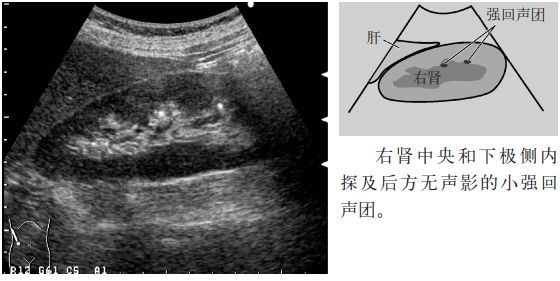

图4 珊瑚状结石

2.占据中心部回声(肾窦)区的大结石称为珊瑚状结石。